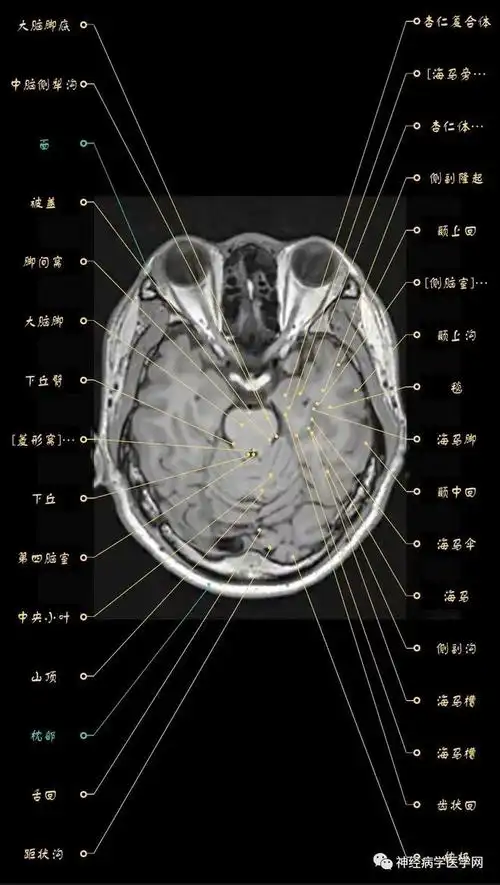

312.头部磁共振影像解剖

高清颅脑mri最全轴位影像解剖人手一册

高清头颅mri断层图谱中英对照案前必备

解剖颅脑丨高清头颅mri断层解剖图谱

脑mri必备丨最详细的脑mri解剖